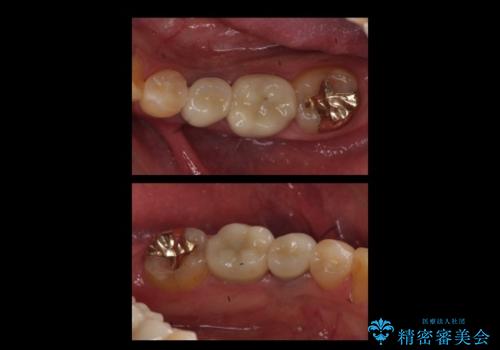

インプラントの向かい合わせの歯や隣の歯の虫歯治療も併せて行なっています。

同時期に治療することで咬み合わせの調整がしやすく、また、適合の良いものを作成できるメリットがあります。

左上6:インプラント(ストローマン)20万円、カスタムアバットメント10万円、スクリューリテイン仮歯2万円、ジルコニアクラウン10万円、ソケットリフト10万円、マイナーGBR 5万円、静脈麻酔(麻酔認定医)5万円

左下5:仮歯 1万円、ジルコニアクラウン10万円、ファイバーコア 2万円

左下6:仮歯1万円、ジルコニアクラウン10万円